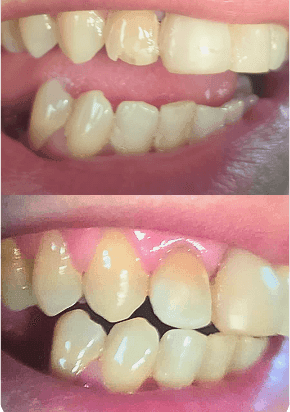

See how our strategies have improved our patients' quality of life and confidence.